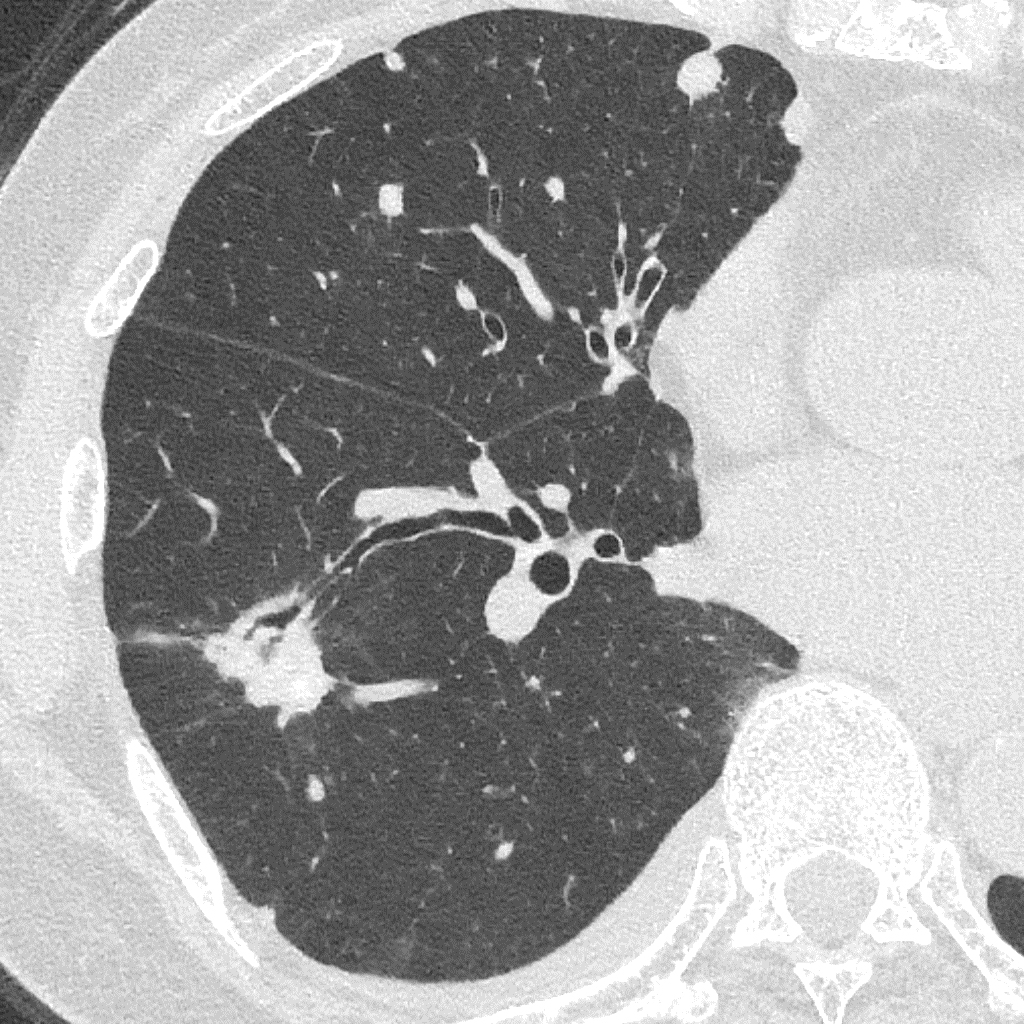

Порівняння звичайної роздільної здатності з ультрависокою роздільною здатністю (УРЗ)²

Звичайна КТ 0,5 мм